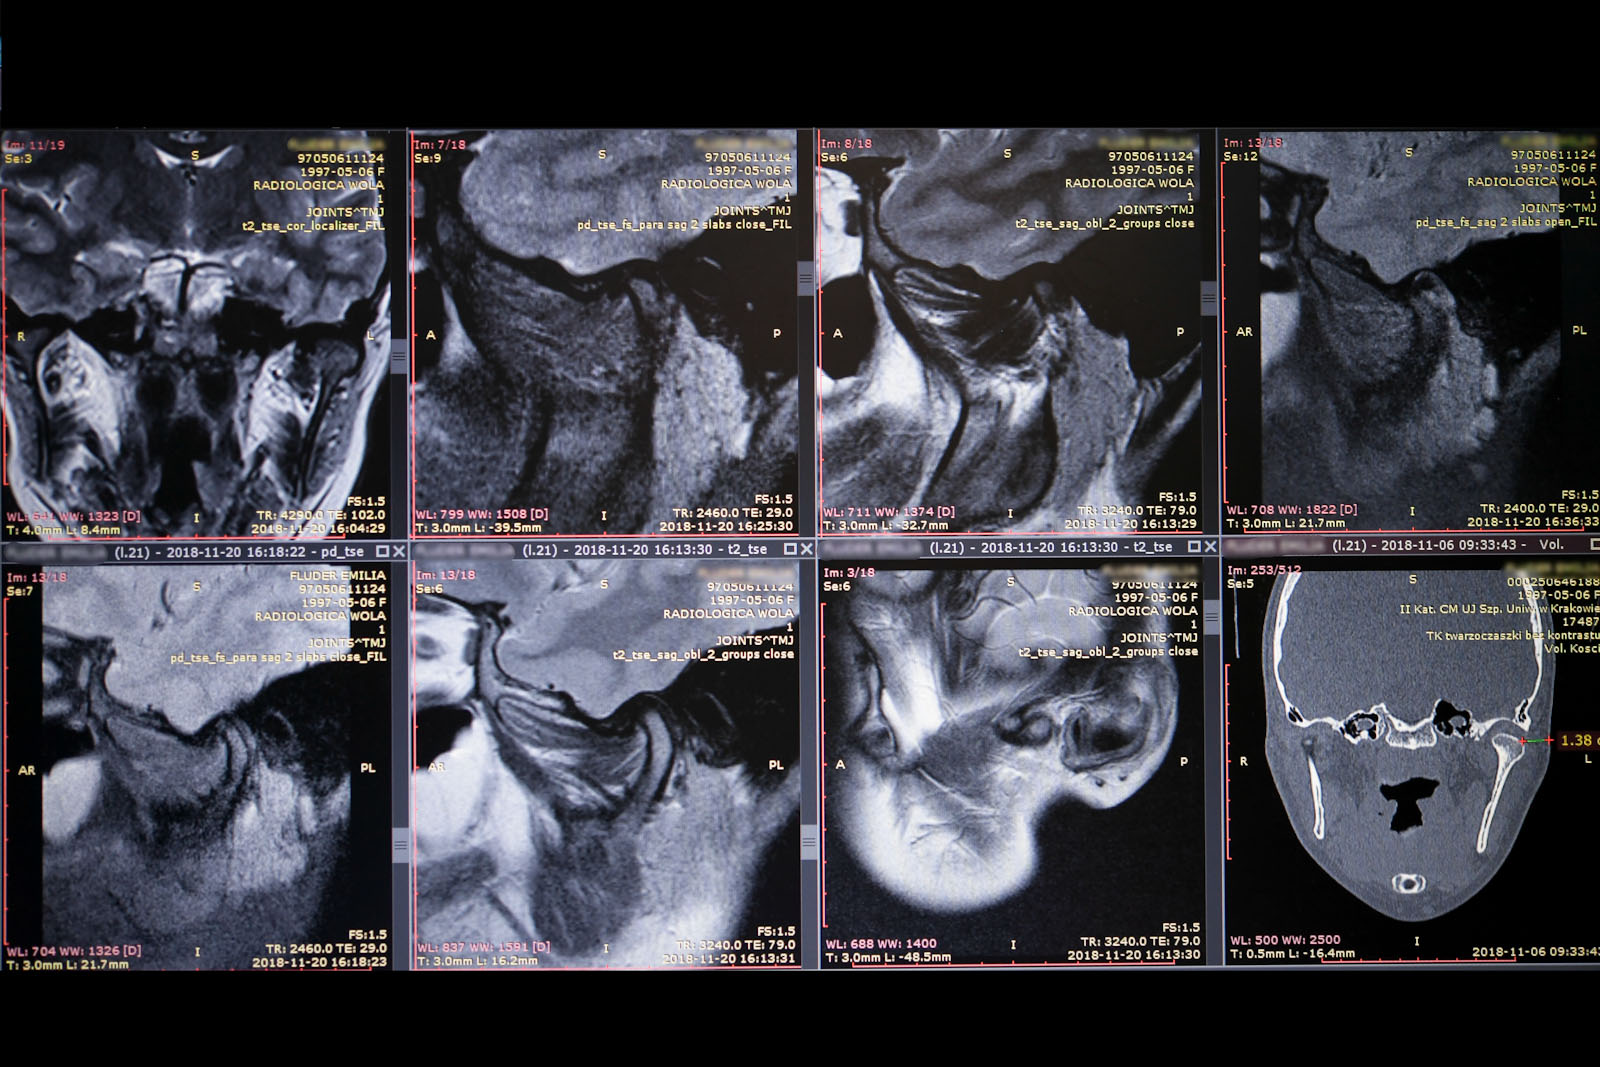

Metoda Gerbera jako punkt wyjścia dla analizy traktuje staw skroniowo-żuchwowy. W relacji do jego funkcji bierze pod uwagę pozostałe ogniwa układu stomatognatycznego. Staw skroniowo-żuchwowy jest działającym synchronicznie symetrycznym elementem anatomii twarzoczaszki, który pozwala na otwieranie ust i funkcje z tym związane. To staw o złożonej budowie, w jego skład wchodzą: dołek stawowy kości skroniowej, który stanowi panewkę stawową, wyrostek kłykciowy, krążek stawowy i torebka stawowa. Krążek zbudowany jest z chrząstki i dzieli jamę stawową na dwie części: górną i dolną. Podczas ruchów opuszczania żuchwy (otwierania ust) krążek stawowy przesuwa się do przodu i dołu. Wraz z krążkiem przesuwa się wyrostek kłykciowy głowy żuchwy po obu stronach. W ruchu przywodzenia żuchwy (zamykania ust) krążek stawowy i wyrostek kłykciowy żuchwy wracają na swoje miejsce do pozycji wyjściowej. Stawy są sprzężone ze sobą czynnościowo (ruch następuje równocześnie w obu stawach) i anatomicznie (łączy je trzon kości żuchwy), stąd też nieprawidłowe asymetryczne obciążenia stawów są najczęstszą z przyczyn zaburzeń narządu żucia.

W ocenie wewnątrzstawowych patologii pomocna jest diagnostyka obrazowa. Konwencjonalne zdjęcia radiologiczne OPG, tomografia komputerowa oraz stożkowa tomografia komputerowa CBCT pozwalają na ocenę elementów kostnych stawu skroniowo-żuchwowego. Ocenę tkanek miękkich zlokalizowanych wewnątrzstawowo umożliwia rezonans magnetyczny NMR.

Norma statyczno-anatomiczna opisuje sytuację skoordynowanego, maksymalnego zaguzkowania zębów przy centralnym położeniu kłykci w dołach stawowych, podczas gdy głowa pacjenta jest utrzymywana swobodnie, pionowo. Przestrzeń stawowa pozostawia odpowiednią ilość miejsca na krążek stawowy oraz na dwie zdrowe warstwy chrząstki, które pokrywają kostne powierzchnie wewnątrzstawowe. Tkanki miękkie wewnątrz, jak i pozastawowe nie są ściśnięte ani naciągnięte.

Norma dynamiczno-anatomiczna opisuje skoordynowaną pozycję, gdzie forma i nachylenie artykulacyjnych powierzchni stawów skroniowo-żuchwowych koresponduje z okluzyjnym nachyleniem zębów.

Norma neuromięśniowa opisuje realną sytuację, kiedy prawidłowa kontrola neuromięśniowa czynności systemu narządu żucia może zostać zaburzona. Uwidacznia się to, gdy podczas maksymalnego zaguzkowania jeden lub oba kłykcie są przemieszczone. Badanie czynnościowe uwidacznia brak harmonii pomiędzy pozycją głów stawowych w stawach skroniowo-żuchwowych i zwarciem. W takiej sytuacji nasila się aktywność mięśni, powodując ich napięcie, czego konsekwencjami są dolegliwości bólowe.